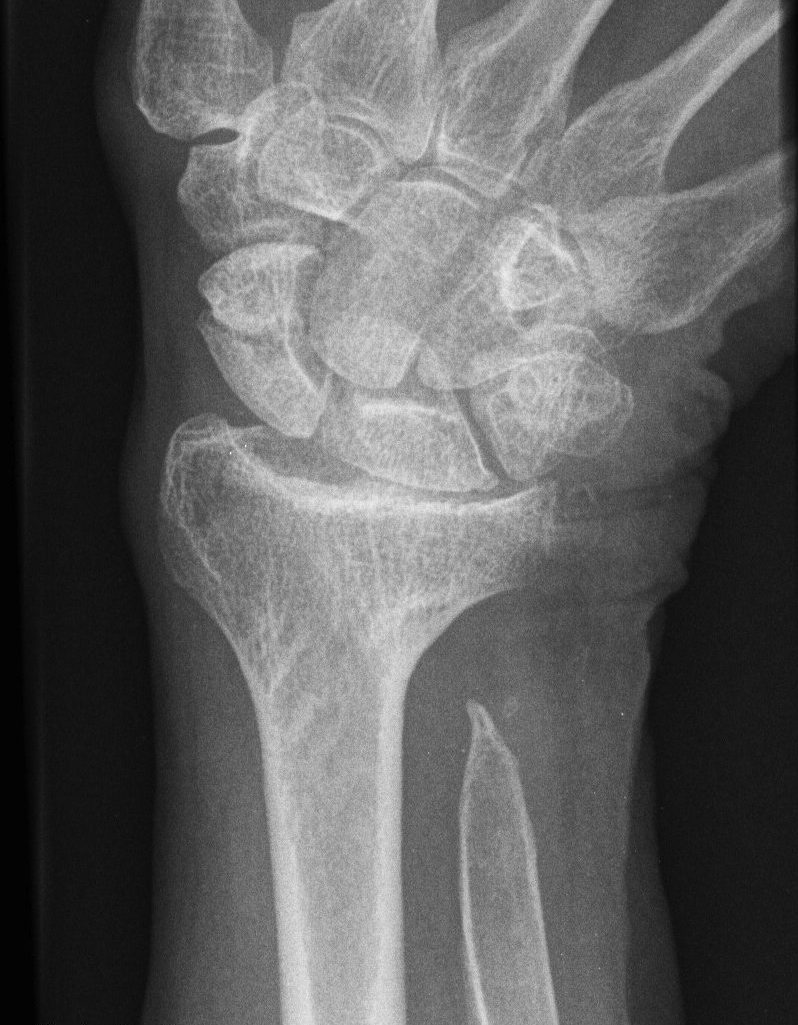

Xray

End stage rheumatoid arthritis of the wrist